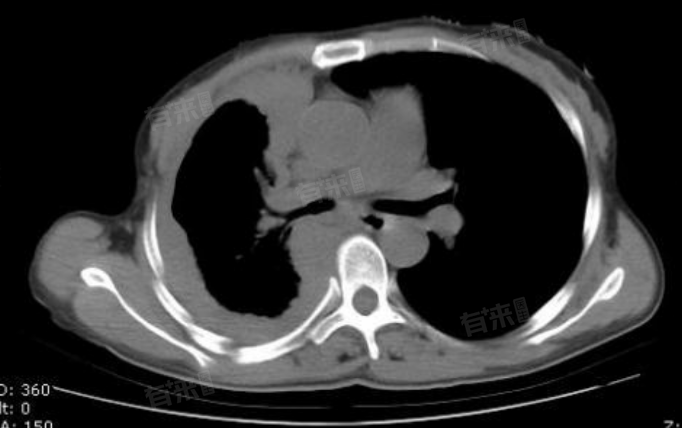

胸膜增厚是一种常见的胸部影像学表现,通常是由于胸膜炎、气胸、胸部外伤、肺部感染等多种原因引起的胸膜炎症反应后,纤维蛋白沉着和肉芽组织增生导致胸膜厚度增加。治疗胸膜增厚需要根据具体病因和病情严重程度选择治疗方法,如一般治疗等,但没有绝对最好。